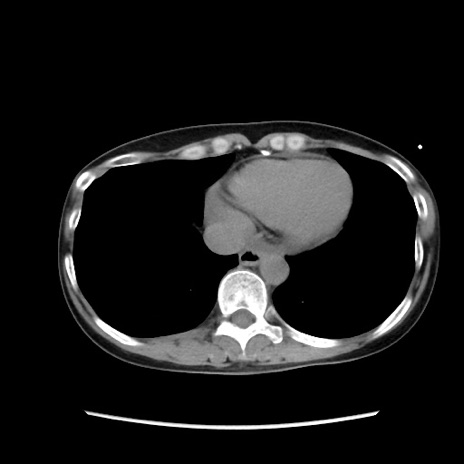

症例32(横断像)

【症例】40歳代 女性

【主訴】上腹部痛、嘔気・嘔吐

【現病歴】約9時間前頃から急に上腹部痛、嘔気、嘔吐が出現。改善しないため救急要請。

【既往歴】子宮頚癌(広汎子宮全摘術、放射線療法)、腸閉塞

【身体所見】腹部:平坦、軟、腸雑音亢進、上腹部を中心に腹部全体に圧痛あり。

【データ】WBC 8400、CRP 0.03